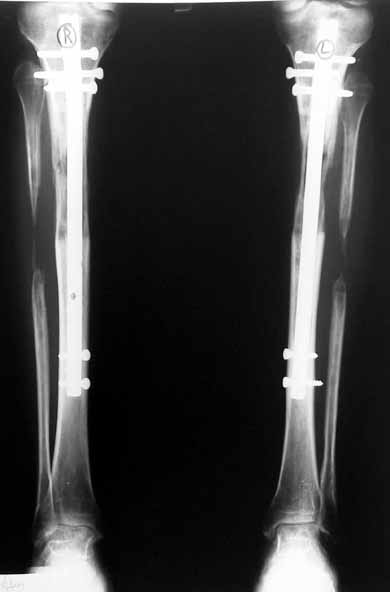

In selected cases, we prefer to use a combination of a unilateral dynamic axial fixator and an interlocked intramedullary nail, in order to protect the length and alignment after the completion of the lengthening procedure. As a prerequisite for this technique, the narowest diameter of the medullary cavity shall be wider than 7 mm and the length of the nail segment distal to the osteotomy site shall be at least 8 cm. after the completion of the lengthening procedure.The intramedullary nail neutralizes shear and bending forces on femur during lengthening, shortens external fixation time, and protects newly formed bone against fractures. In our series, subtrochanteric osteotomy was performed in one case. No varus angulation occured despite the intramedullary nail.

Despite low sample size, our aim was to compare two groups with matching ethiology, age, location and amount of the deformity and other similar factors. We neglected simultaneous tibial lengthening and osteotomy site in this preliminary study. The sample size was not enough to conduct a prospective randomized trial. Although the results of the study did not produce statistically significant data, it is the first and only example in our country and conveys significant experience.

The combination of intramedullary anil and dynamic axial external fixator is harder as a technique than Standard Ilizarov applications. However, it is stil appealing due to the following advantages: shortening of the duration of external fixation, protection against refracture, early rehabilitation, gaining maximum range of motion and daily quality of life. These advantages are more important than disadvantages such as increased cost, increased blood loss and potetntial deep infection. All in all, we believe that the technique of femoral lengthening over an intramedullary nail is a safe and reliable method and provides advantages over standard Ilizarov aplications.